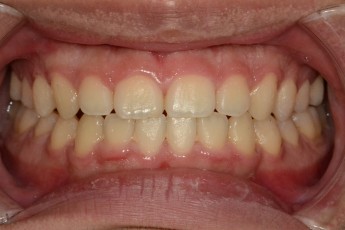

After